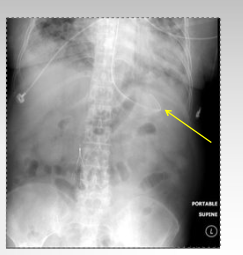

what type of tube is this?

NG tube